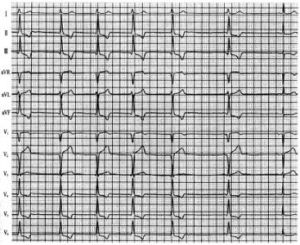

加速性心室自主心律(AIVR)為異位的心室節律,至少連續3次以上的心室搏動,其頻率超過心室正常的固有頻率(30~40次/min),但慢於其他室性心動過速的頻率。它的出現並非突發突止,而是逐漸的,其頻率與基礎心律差不多,常輪流主宰心搏,每於基礎心律過緩時出現,其偶聯間期比一般的室早為長,節律可能與基礎心律呈干擾性房室分離,或間有心室奪獲或融合波,頻率一般不超過120次/min,為單形性,也有多形性的,一般持續時間不長(數分鐘以內),終止也是緩慢的,或是以基礎心律加速,超過室性心律而終止,也可能室性心律減慢,讓位給基礎心律而終止[1]。本例患者102歲高齡,Holter檢查基礎心律為心房顫動,AIVR與其反覆交替出現,完全符合上述特點,尚未見有類似文獻報導。

AIVR是潛在起搏點自律性增強所引起的異位心律失常,常見器質性心臟病患者,如冠心病、風濕性心臟病、心肌病、急性心肌炎、高血壓心臟病、洋地黃和其他藥物中毒以及急性心肌梗死溶栓治療再灌注時等,少數可發生於沒有明顯器質性心臟病患者。它本身是“良性”的,一般不致引起明顯血流動力學障礙,也不會發展為室顫。但應考慮具體患者不同情況與嚴重程度,本例老年患者102歲高齡,有明顯心肌缺血、肺部感染、心功能較差,有室早及短陣室速發作,且出現較長時間的AIVR,肯定不屬於良性,預後不佳,應引起足夠的重視,積極治療肺部感染,改善心肌供血,防止心功能的惡化。